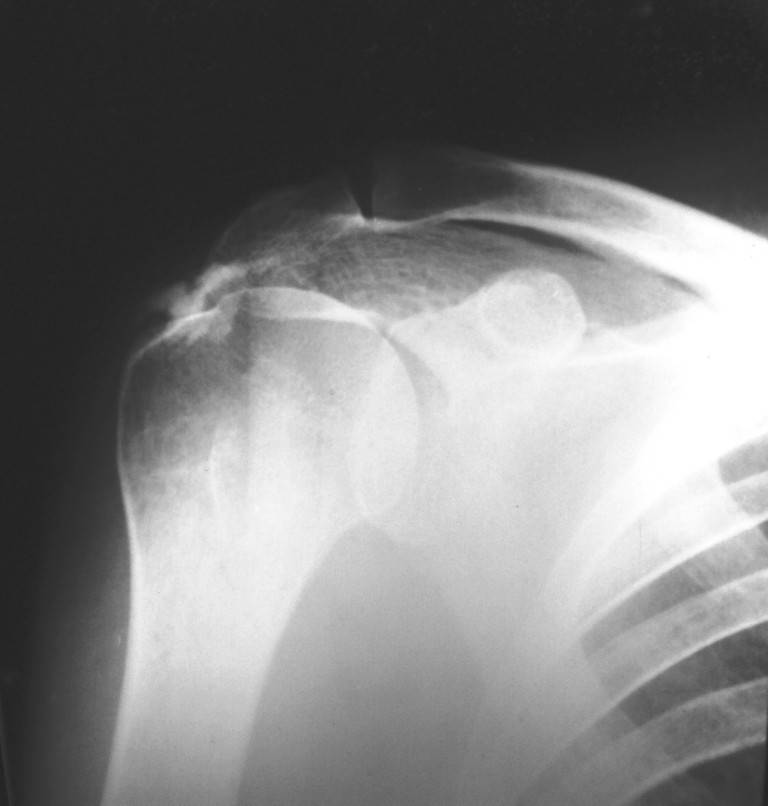

Уважаемые коллеги! Поздравляю всех с наступившим Новым Годом, наступающим праздником Светлого Рождества Спасителя, и прошу помощи в виде ваших комментариев по представленному мною рентгеновского снимка правого плеча. Женщина, 1959 г.р.. Жалоб на функцию правого плечевого сустава не предъявляет, движения в полном объеме, активные и пассивные без ограничений и боли. Меня смущает на данном снимки состояние головки.Сам снимок был проведен с целью контроля состояния сустава, так как больная в 2003 году проходила у меня лечение по поводу правостороннего осифицирующего тендинита надостной мышцы. Если потребуются снимки 2003г. скажите и я размещу.

Меня смущает на представленном снимке <просветление> в области бугра и головки плеча. Или это только мои необоснованные сомнения?

А что вас смущает7 Остеопороз бугорка? Так это следствие хронического инсерционита вращателной манжеты. Сделайте снимок в более мягком, чем здесь режиме.

"Меня смущает на представленном снимке "просветление" в области бугра и головки плеча. Или это только мои необоснованные сомнения?"

На первый взгляд непохоже на агрессивный процесс. Возможно, из-за качества снимков, но мне кажется, что на лопатке и на ключице имеются какие то аномальные пятна?

Отсутствие процесса в других участках тела и отсутствие жалоб, наличие характерной локализации, говорит о том, что процесс напоминает ?псевдокисту" головки плеча.

Кроме головки плеча "псевдокиста" встречается еще в передних отделах пяточной кости.

На фоне клинического благополучия, процесс обычно диагностируется в случайных рентген исследованиях.

Из-за отсутствия типичного воспалительного процесса в костномозговой части в Магнето Резонансовых Исследованиях "псевдокиста" показывает нормальный сигнал, поэтому первоочередно необходимо сделать качественные ренген снимки, которые увеличат шансы заметить случайные ?аномальные" находки и установить правильный диагноз.

Конечно, снимки с отведением не помешали бы, но кроме остеопороза у больной других патологических изменений нет